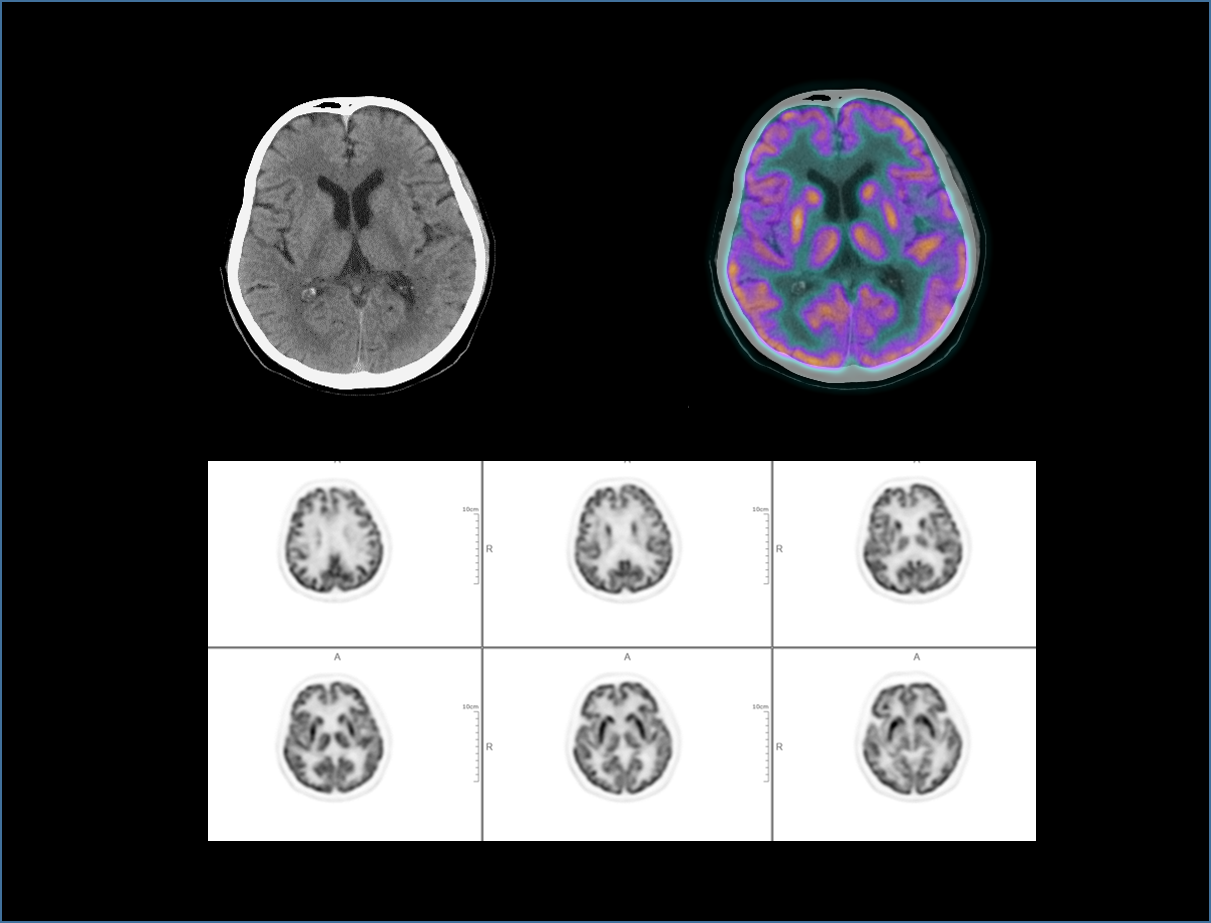

全真数字PET与160层北斗CT强强联手,将高品质的功能影像与解剖学影像精准融合,显著提升微小病灶检测精度,全面助力肿瘤、心脏和神经等重大疾病领域的精准诊疗。

成就至臻高清PET影像

全真PET影像链

2.9mm NEMA分辨率

硬件源头提升空间分辨率近40%*

HYPER Iterative®4D全迭代算法

软件算法保障PET图像高清还原